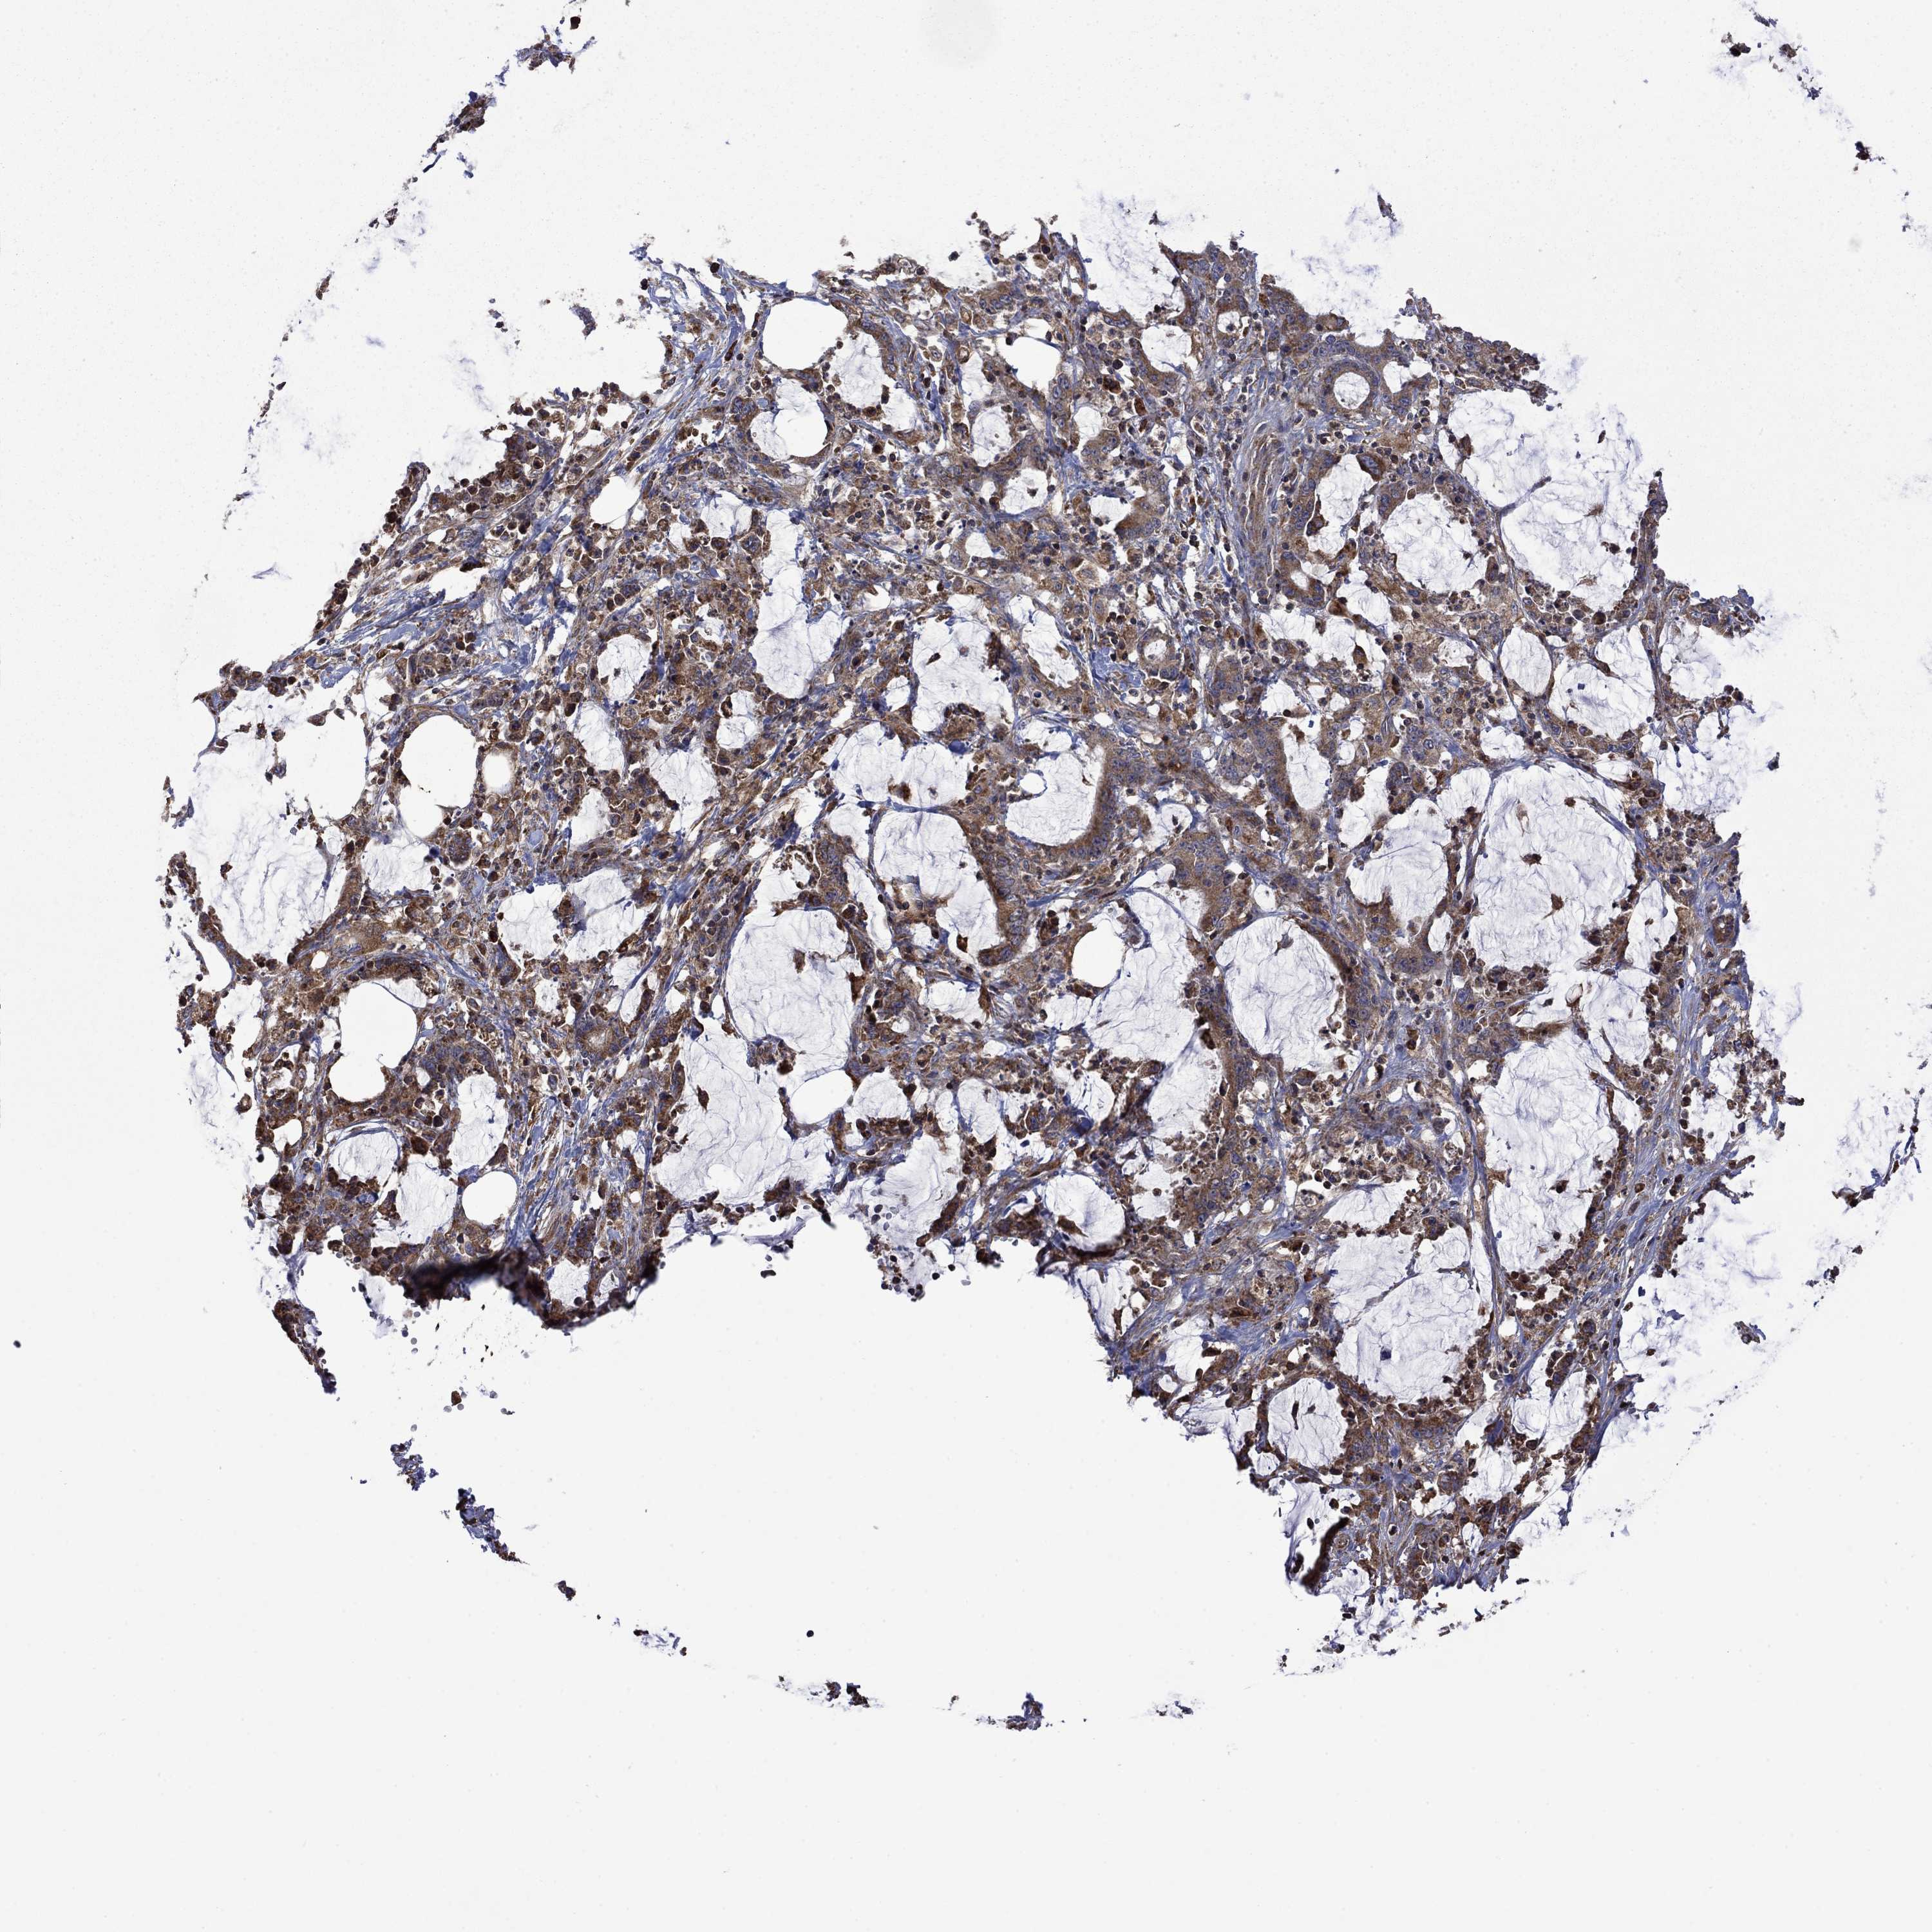

STOMACH CANCER - Protein expressioni

A mouse-over function shows sample information and annotation data. Click on an image to view it in a full screen mode. Samples can be filtered based on level of antibody staining by selecting one or several of the following categories: high, medium, low and not detected. The assay and annotation is described here.

Antibody stainingi

Antibody staining in the annotated cell types in the current human tissue is reported as not detected, low, medium, or high, based on conventional immunohistochemistry profiling in selected tissues. This score is based on the combination of the staining intensity and fraction of stained cells.

Each image is clickable and will lead to virtual microscopy that enables deeper exploration of all samples and also displays staining intensity scores, fraction scores and subcellular localization as well as patient and tissue information for each sample.

Antibody HPA067869

Antibody CAB009499

Staining

High

Medium

Low

Not detected

Intensity

Strong

Moderate

Weak

Negative

Quantity

>75%

75%-25%

<25%

None

Location

Nuclear

Cytoplasmic/membranous

Cytoplasmic/membranous,nuclear

Adenocarcinoma, NOS

Adenocarcinoma, High grade